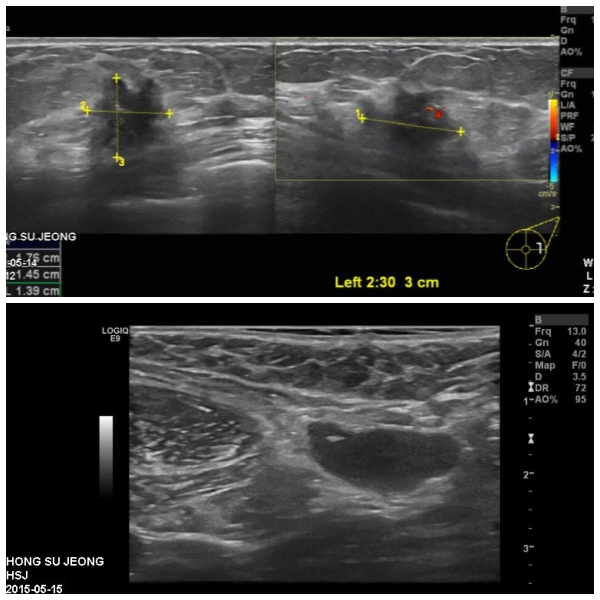

좌측 유방에 만저지는 몽우리로 내원하신 50대 여성분으로 유방 초음파 시행후,

좌측 유방 2시30분에서 3cm 떨어진 거리의 혹과, 겨드랑이 림프절 비대 부위

조직검사 시행하여 좌측 침윤성 유관암과, 겨드랑이 전이로 확인 되었습니다.